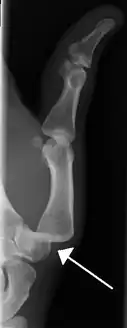

• Finger: Interphalangeal (IP) or metacarpophalangeal (MCP) joint dislocations[31]

• In the United States, men are most likely to sustain a finger dislocation with an incidence rate of 17.8 per 100,000 person-years.[32] Women have an incidence rate of 4.65 per 100,000 person-years.[32] The average age group that sustain a finger dislocation are between 15 and 19 years old.[32]